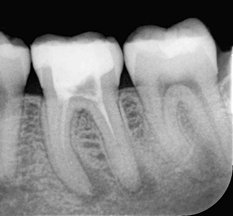

Wurzelkanalbehandlungen sind komplex. Es müssen auch feinste Wurzelkanäle gefunden, gereinigt und vollständig gefüllt werden. Im AD Zahnzentrum Dortmund werden daher Wurzelkanalbehandlungen von speziell ausgebildeten Zahnärzten (Endodontologen) durchgeführt. Modernste Technik unterstützt die Behandlung. Beispielsweise arbeiten die Experten unter einem hochauflösenden OP-Mikroskop oder vermessen die Wurzelkanäle elektronisch (Endometrie). Die hier zu sehenden Röntgenaufnahmen verdeutlichen, wie entscheidend kleinste Details für den Behandlungserfolg sein können.

Auf dem linken Bild ist eine unvollständige Wurzelfüllung erkennbar. Die dünne weiße Linie endet deutlich vor der Wurzelspitze. Die dunklen Schatten im Bereich der Wurzelspitzen weisen auf eine erneute Entzündung hin. Das rechte Bild zeigt denselben Zahn nach einer erneuten Behandlung (Revision). Alle Wurzelkanäle wurden vollständig gereinigt und bis zur Wurzelspitze dicht verschlossen – die Prognose für den Zahnerhalt ist dadurch sehr positiv.